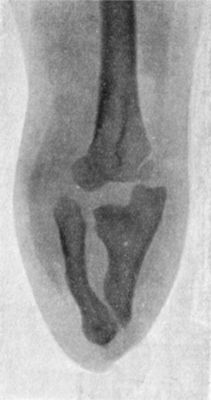

| 39. | Forward Dislocation of Elbow, with Fracture of Olecranon | 93 |

| 40. | Radiogram of Forward Dislocation of Head of Radius, with Fracture of Shaft of Ulna | 95 |